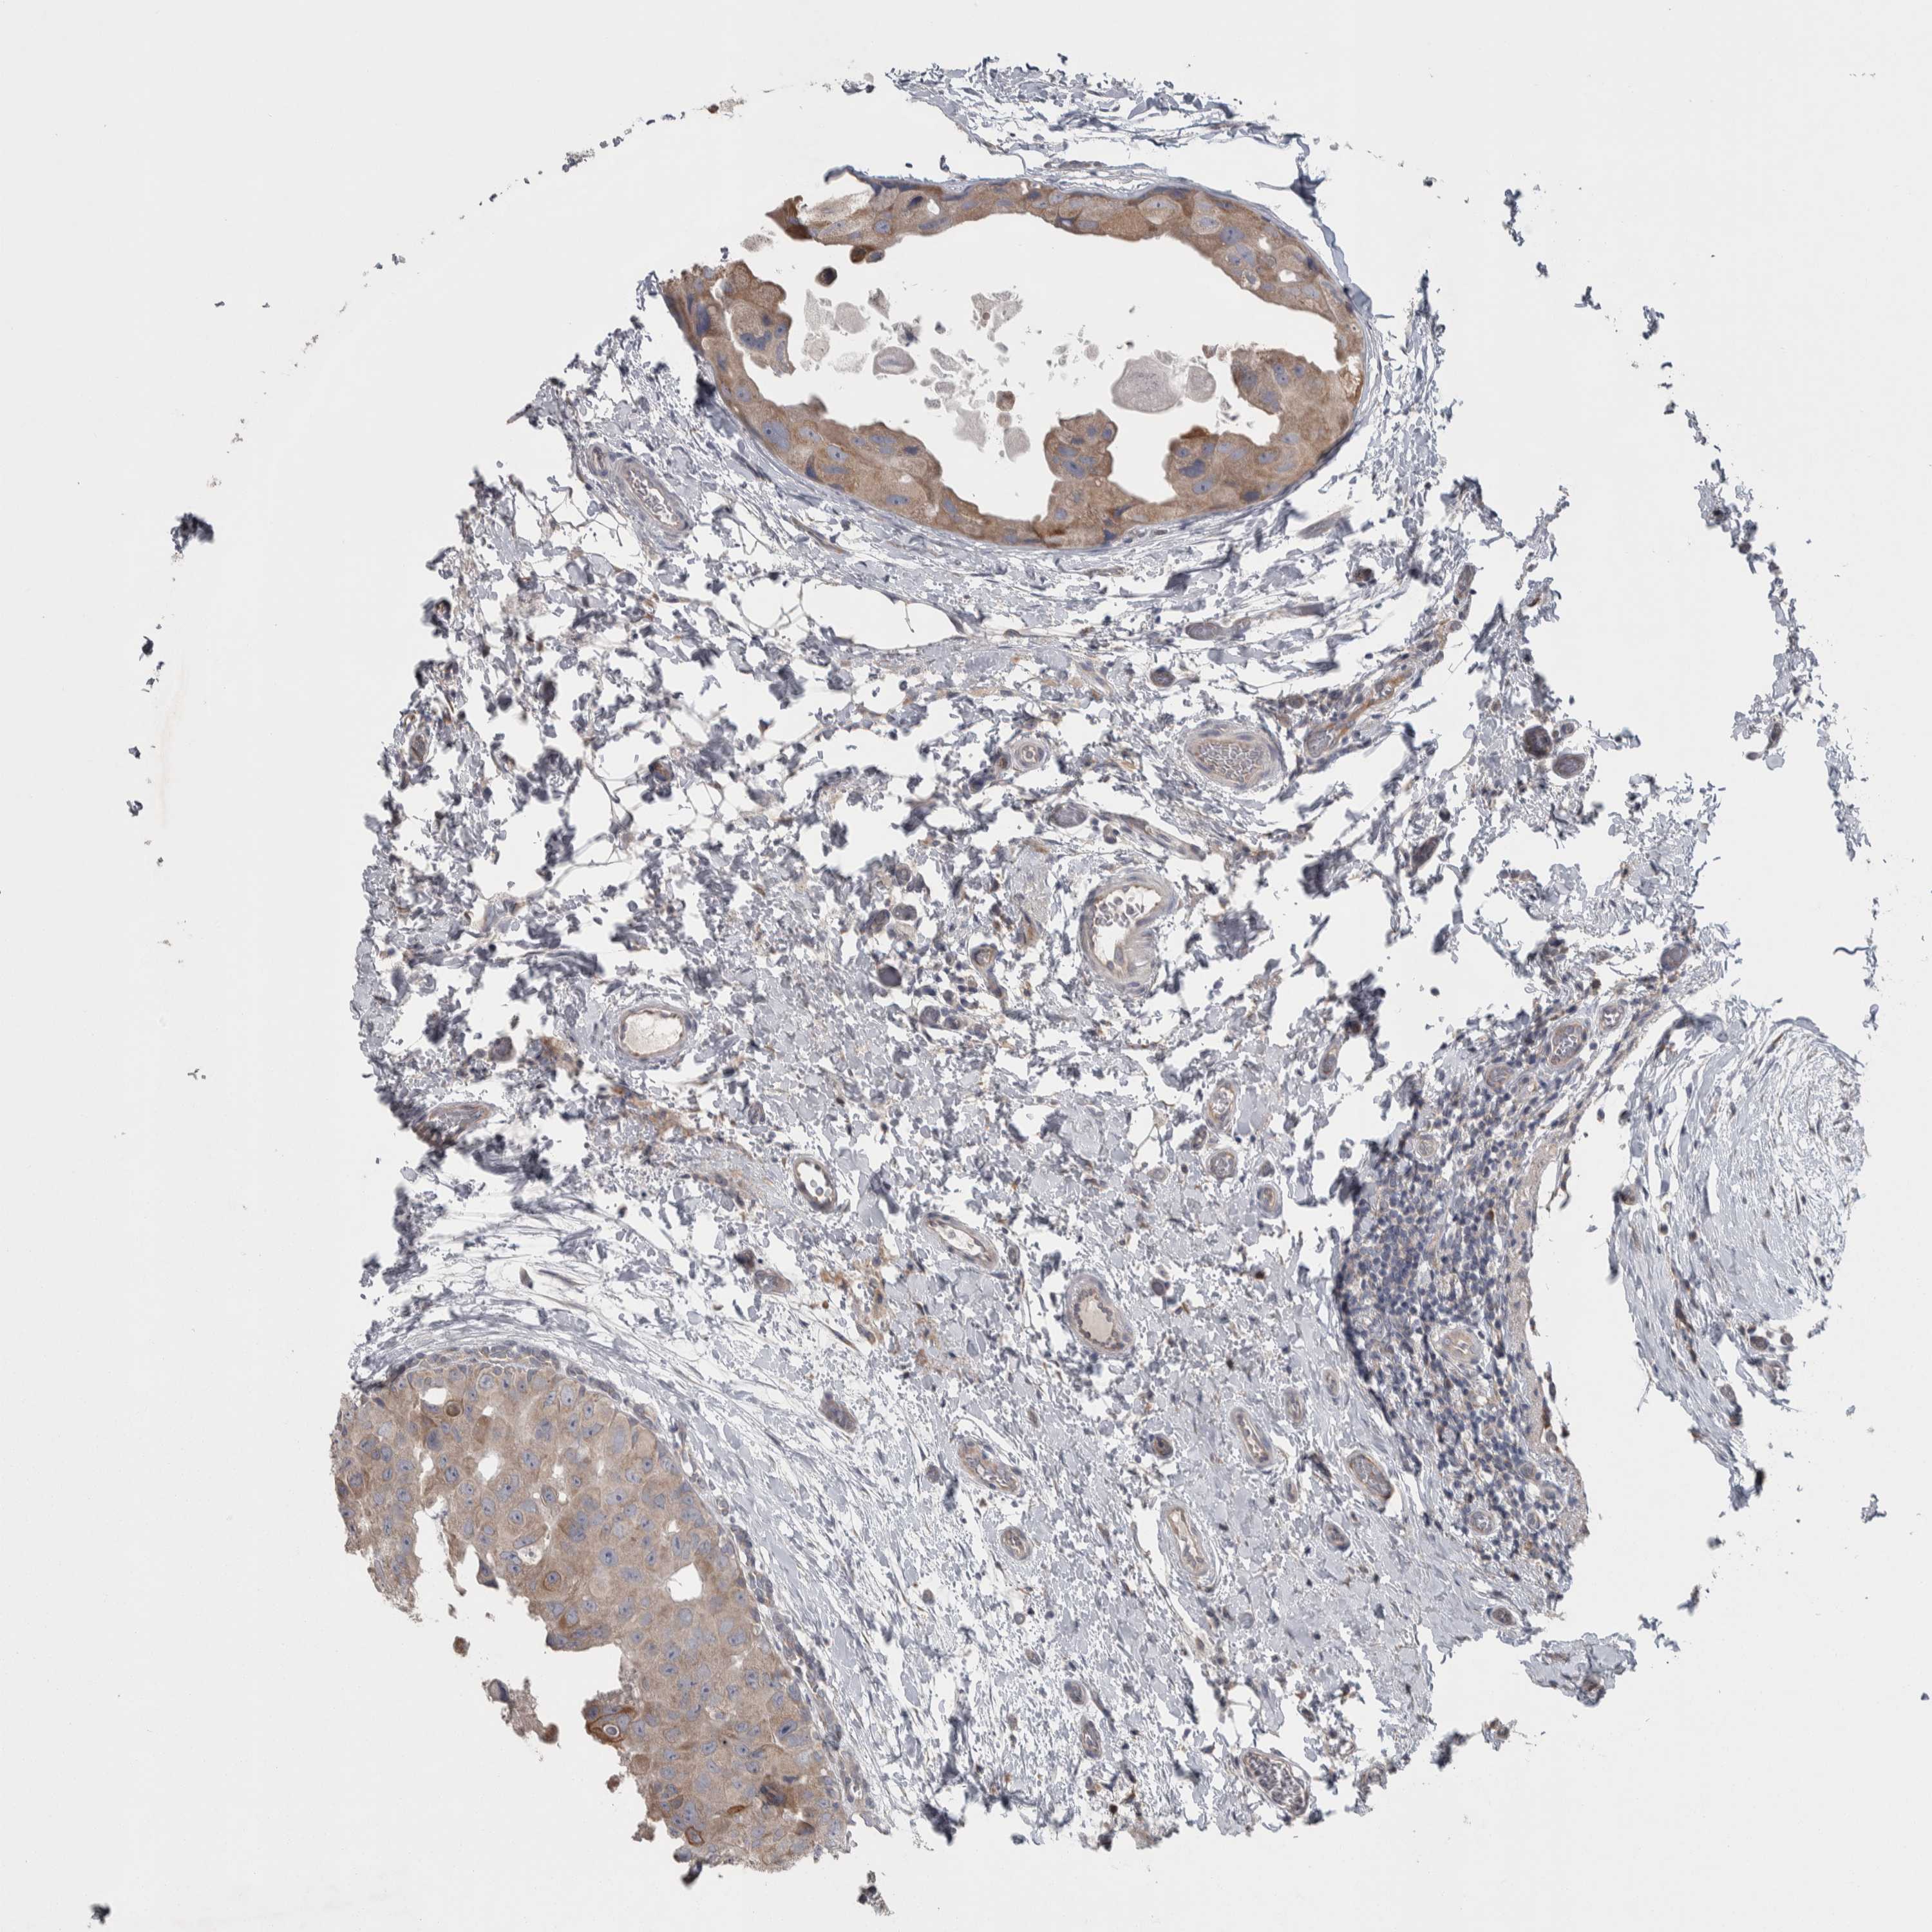

Breast cancer

Human cancer